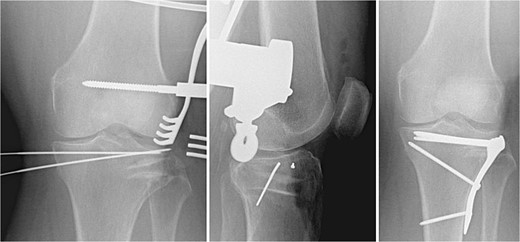

Tricortical iliac crest allograft preparation and insertion

The void left in the lateral tibial condyle after elevation of the articular surface is usually triangular in shape. The depth and lateral height are measured. A tricortical iliac crest allograft is selected and cut to an appropriate size based on these measurements. The allograft is then inserted parallel to the joint surface to raft the articular surface. They usually fit nicely thanks to the natural triangular shape of the allograft (Fig. 2).

Tricortical iliac crest allograft preparation, measurement, cut to an appropriate size, and insertion into the defect.